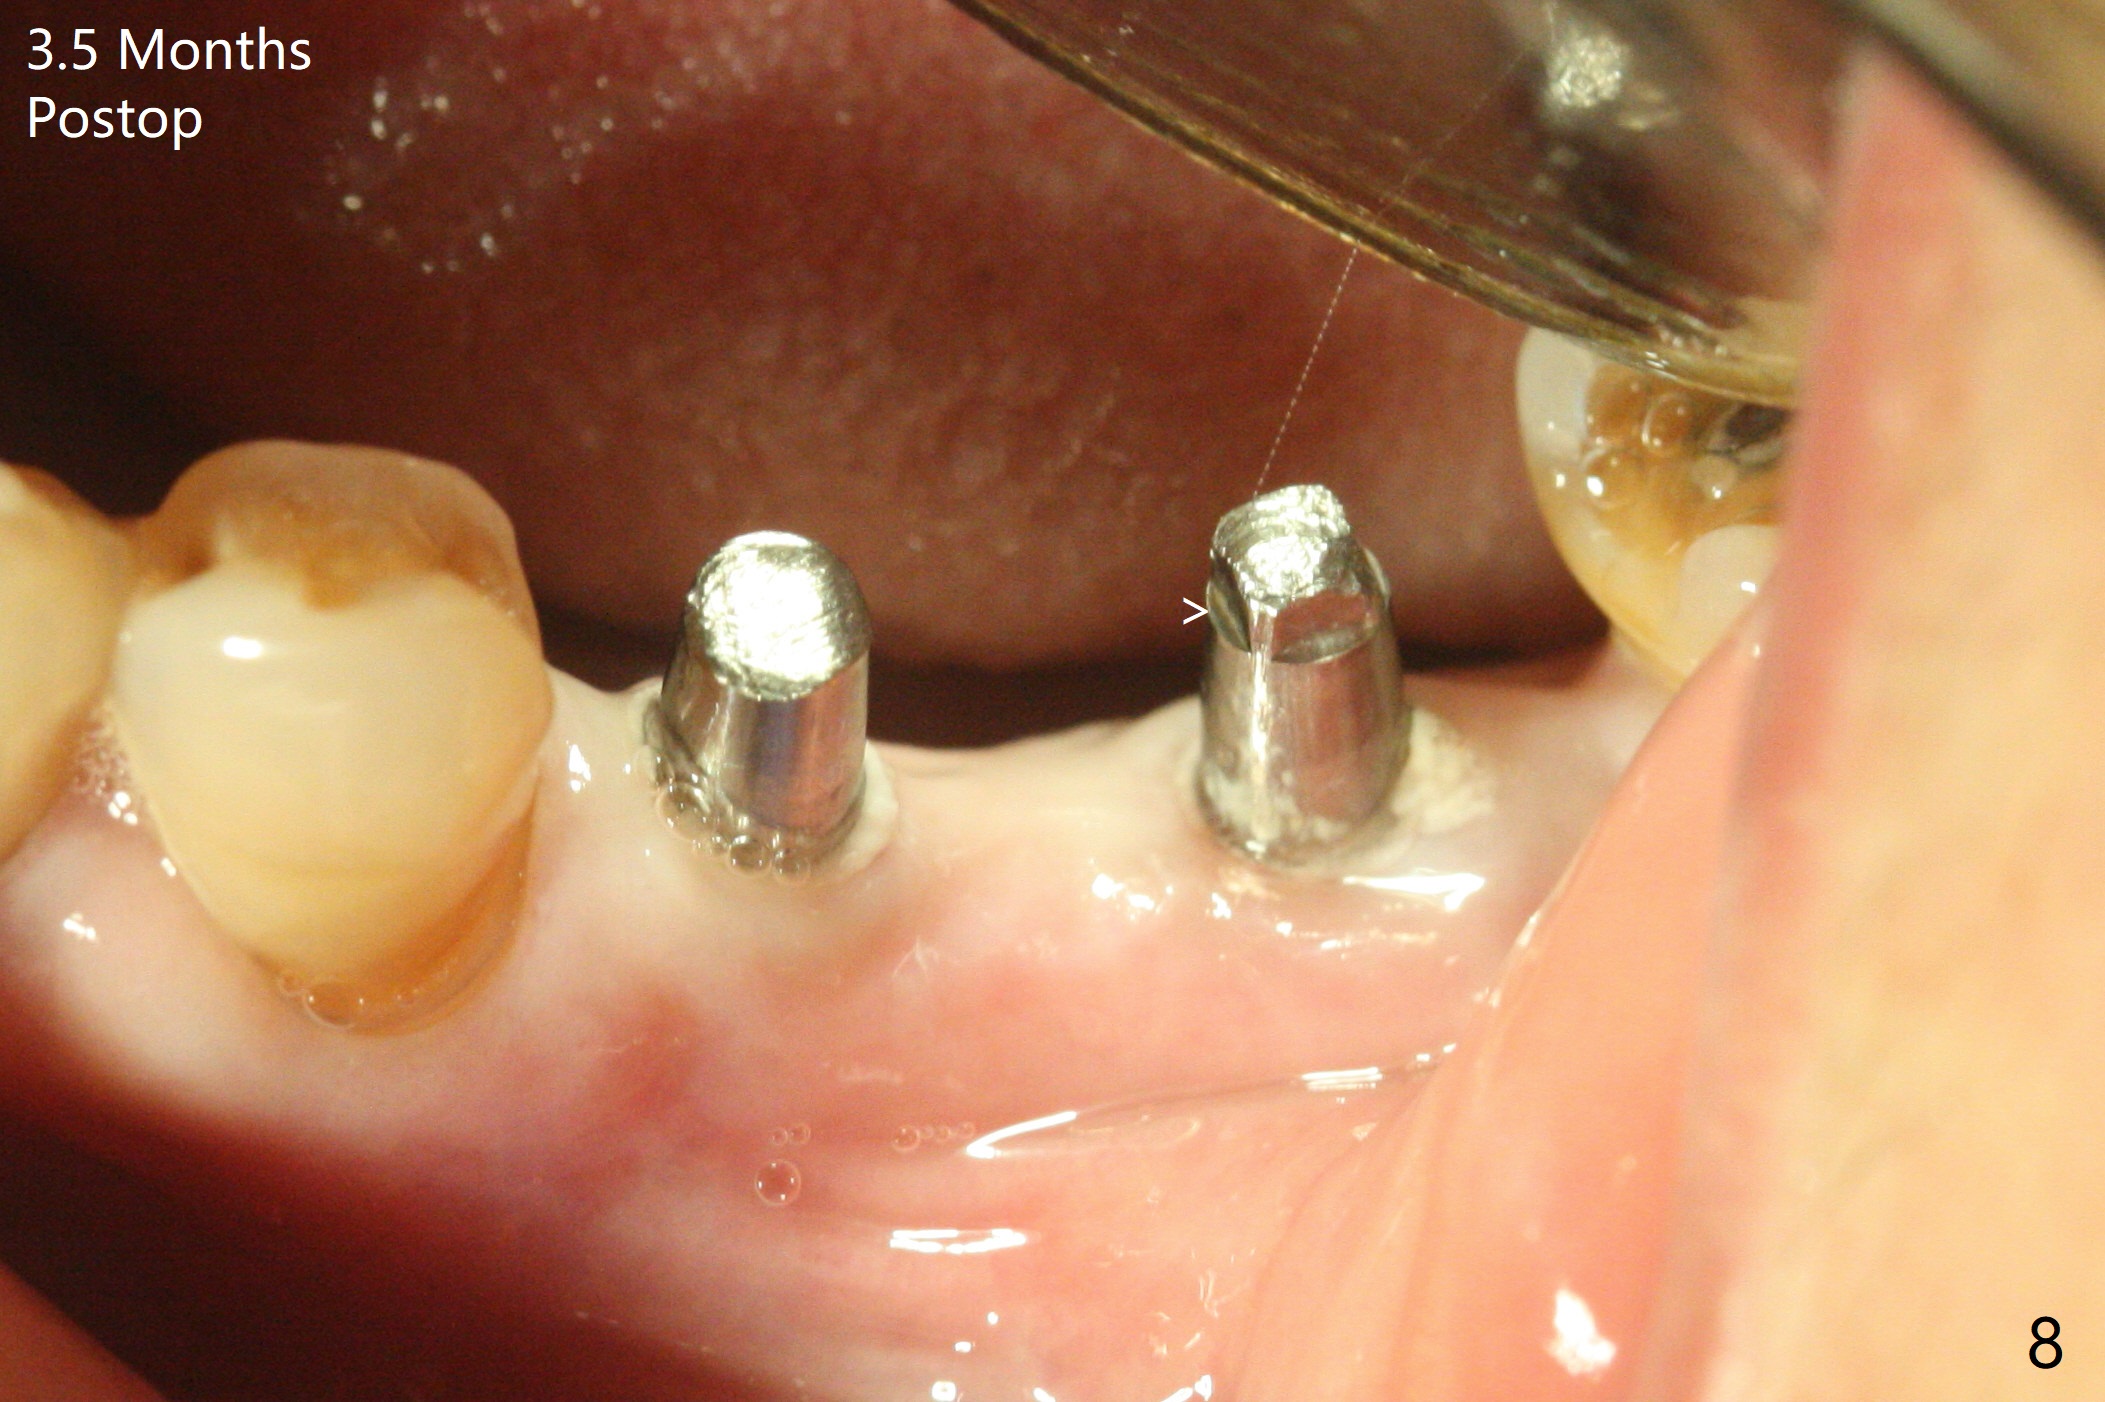

左下5,6切开,使用导板钻洞,都偏向颊侧(图一),好像牙槽嵴太狭窄,不适合做劈开术,然后改为自由手,使用Lindermann(侧方)钻头将钻洞往舌侧迁移,完成一段式植体初步钻洞(图二)以及植体植入(图三:2.5毫米(直径),根据近远中距离,植体不显得太窄)。尽管下齿槽神经阻断麻醉(开始浸润麻醉),病人疼痛明显,不敢下沉远中植体太多(图四:>),放置粘性骨块(图五,六:*)和PRF膜。缝合后,调整基台以及对合牙高度(图六: <),最后放置牙周敷料。由于植骨,术后15天植体周围形成致密的牙龈带(图七:*(gingival band))。术后一个月安置临时连体牙冠,没有任何咬合接触,主要目的防止7近中倾斜。术后三个半月临时牙冠被吞入,右侧托牙也不见了,局部牙龈健康,塞入2-0 gingival retraction cord(增加5基台长度(今后牙冠固位),图八 (>:植体螺丝刀终止地方)),取模。永久性牙冠边缘不重要,由实验室决定。清除残余粘固剂也不是很困难(图九)。